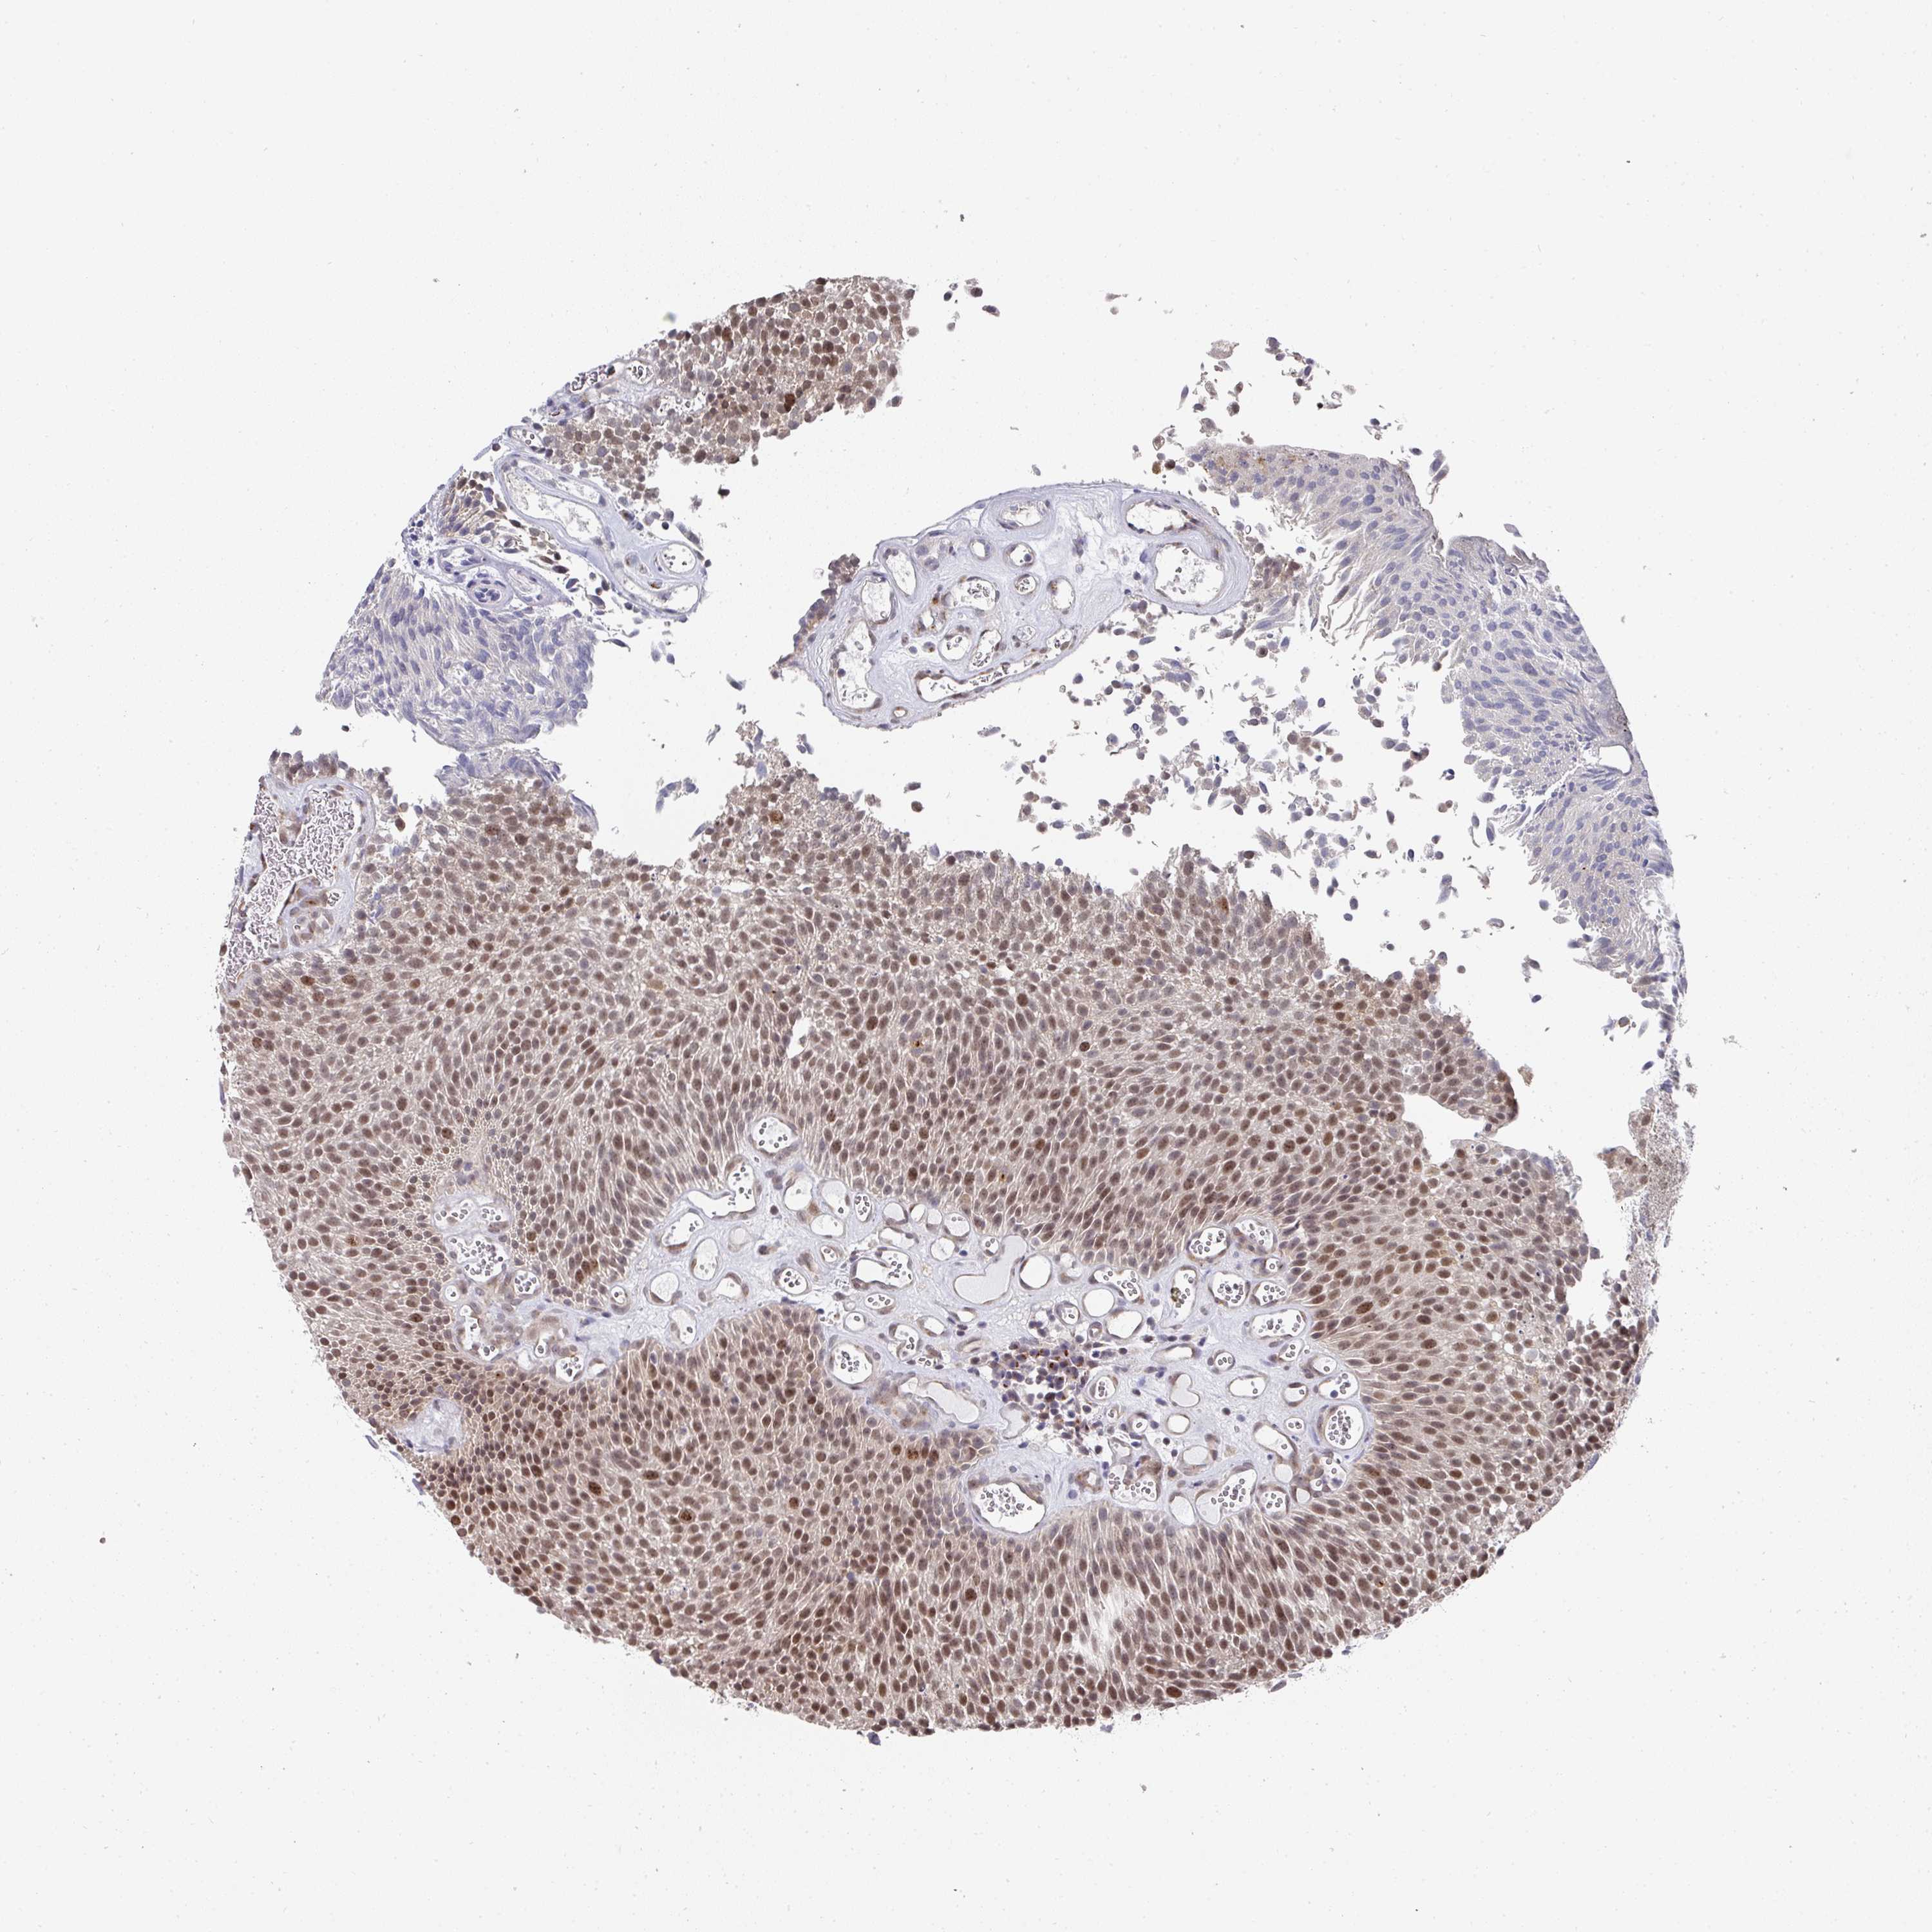

UROTHELIAL CANCER - Protein expressioni

A mouse-over function shows sample information and annotation data. Click on an image to view it in a full screen mode. Samples can be filtered based on level of antibody staining by selecting one or several of the following categories: high, medium, low and not detected. The assay and annotation is described here.

Note that samples used for immunohistochemistry by the Human Protein Atlas do not correspond to samples in the TCGA dataset.

Antibody stainingi

Antibody staining in the annotated cell types in the current human tissue is reported as not detected, low, medium, or high, based on conventional immunohistochemistry profiling in selected tissues. This score is based on the combination of the staining intensity and fraction of stained cells.

Each image is clickable and will lead to virtual microscopy that enables deeper exploration of all samples and also displays staining intensity scores, fraction scores and subcellular localization as well as patient and tissue information for each sample.

Antibody HPA051314

Staining

High

Medium

Low

Not detected

Intensity

Strong

Moderate

Weak

Negative

Quantity

>75%

75%-25%

<25%

None

Location

Nuclear

Cytoplasmic/membranous

Cytoplasmic/membranous,nuclear

Urothelial carcinoma, High grade

Urothelial carcinoma, NOS

Urothelial carcinoma, Low grade